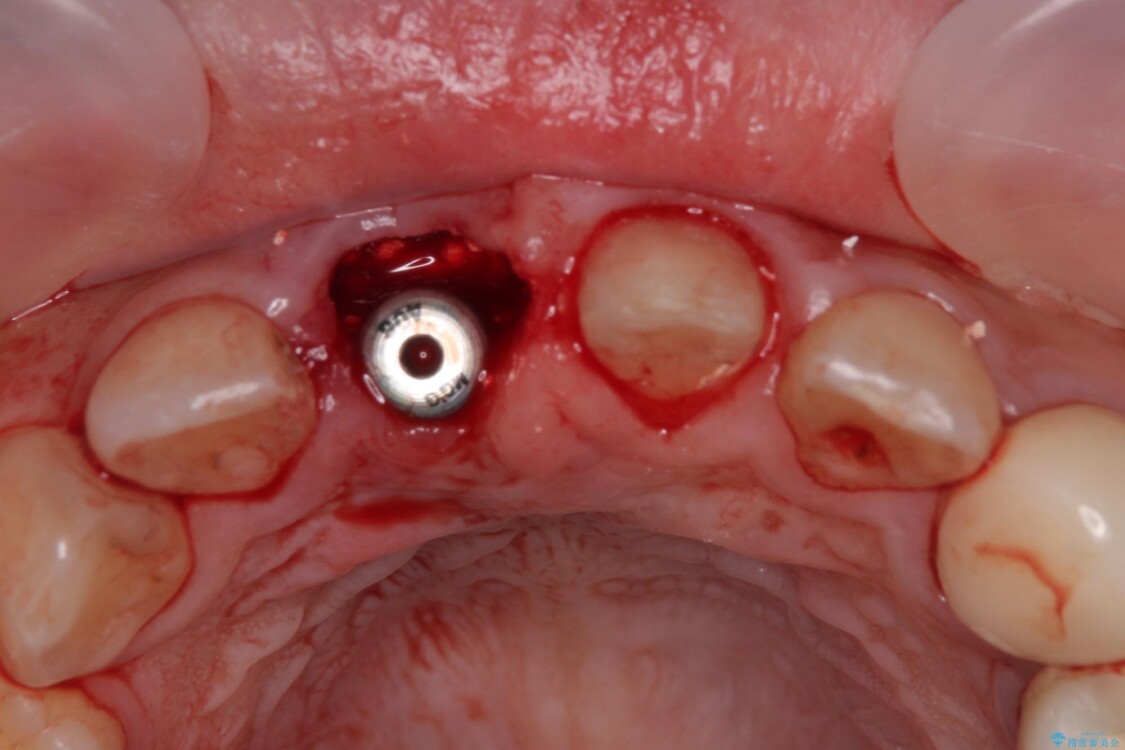

▶右上中切歯

抜歯後、即時インプラント埋入

審美性を考慮し、仮歯を即日装着

治療期間を最小限に抑えつつ、自然な前歯のラインと歯ぐきの形を維持

治療途中

• 「抜歯してブリッジ」と言われた20代女性が選んだ治療とは|たった4か月で自然な笑顔に抜歯即時インプラント+審美補綴の症例 治療途中画像